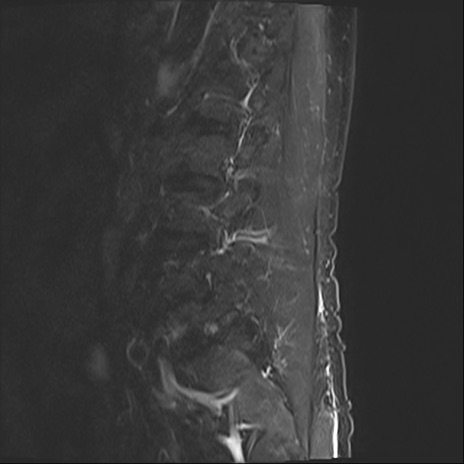

【整形】TIPS症例2 腰椎MRI STIR(矢状断像)

【症例】70歳代男性

【主訴】左下肢痛

【現病歴】2週間前くらいから腰痛、左下肢痛あり。左臀部から大腿、下腿外側のしびれが常時ある。歩行とともに同部位の痛みあり。

【身体所見】Lasegue70-/60+、Bragard-/±、PTR ±/±、ATR -/-、IP 5/5、TA 5/4、TS 5/5、EHL 右第1足趾なし/3、FHL 5/5、hypersthesia(-)、足背動脈触知良好

異常所見と診断は?